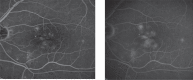

Figure 5

Imaging of diabetic macular oedema. Mid (a) and late (b) phase fluorescein angiogram images showing leaking microaneurysms and pooling of dye in intraretinal spaces.